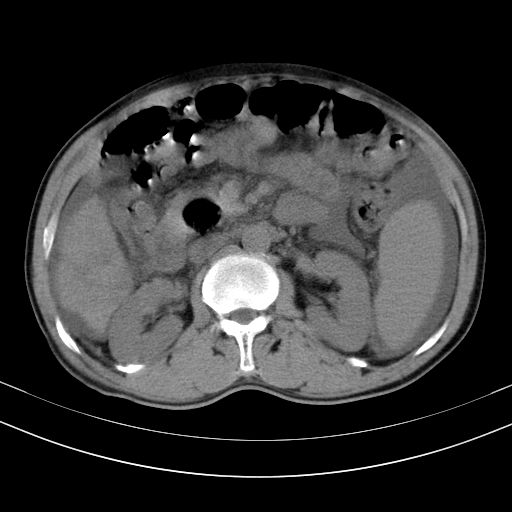

以下是引用随光逐影在2010-2-28 10:23:00的发言:[br]1)考虑肝癌;建议行ct增强扫描检查。2)肝硬化,脾大,腹水。3)慢性胆囊炎。

以下是引用dyqct在2010-2-28 16:44:00的发言:[br][quote]以下是引用随光逐影在2010-2-28 10:23:00的发言:[br]1)考虑肝癌;建议行ct增强扫描检查。2)肝硬化,脾大,腹水。3)慢性胆囊炎。